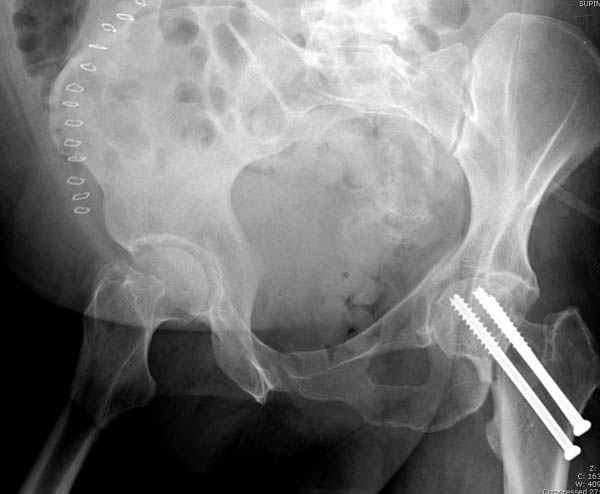

Перелом шейки смогли зафиксировать через пару дней, ацетабулум до сих пор не оперирован, на вытяжении.

Из-за упущенного времени (три недели с момента

поступления) ацетабулум ведем консервативно.

На снимке ацетабулума редко встречающийся очень низкий перелом, наверное, трудно было репозицию через один доступ? Перелом как бы замкнулся в квадрилатеральной поврехности.